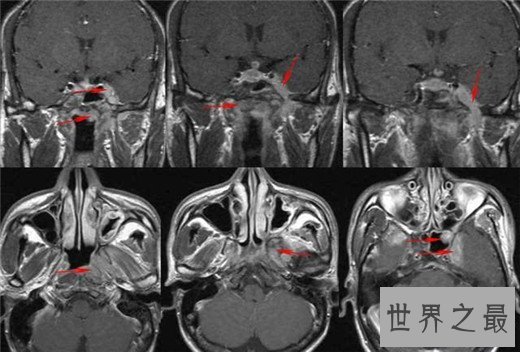

8、鼻咽癌

鼻咽癌在我们国家恶性肿瘤里面,发病人数占到了大约三成左右,是中国十大高发恶性肿瘤之一,很多人都不知道他患了鼻咽癌,因为鼻咽癌的早期症状是不明显的,鼻咽癌形成的主要原因是因为一些慢性疾病,比如说鼻炎之类的,另外就是病毒性感染,最后一个就是喜欢吃腌腊制品。虽然说鼻咽癌他很难发现,但他治愈几率是很大的,大概有60%左右。